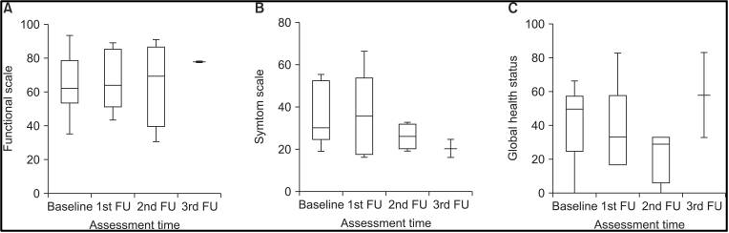

לא נמצאו הבדלים מובהקים באיכות החיים הקשורה לבריאות (HRQoL) בזמן ההערכה במטופלים שיכלו לענות על השאלון, הן EORTC QLQ-C30 (איור 3) והן FACT-Hep (איור 4). ציוני איכות החיים הקשורים לבריאות (HRQoL) נטו בדרך כלל להשתפר עם המעקב. עם זאת, סטטוס הבריאות הגלובלי (global health status) וסולמות הסימפטומים (symptom scales) של EORTC QLQ-C30 ירדו מעט במהלך המעקב.

להלן איור 3: שינוים ב-EORTC QLQ-C30, תתי סולמות מקו הבסיס ל3 חודשים לאחר טיפול קרינתי לכל הכבד בשילוב עם היפרתרמיה. (A) סולם תפקודי, (B) סולם סימפטומים, (C) סטטוס בריאות גלובלי.

לא נמצאו הבדלים מובהקים באיכות החיים הקשורה לבריאות (HRQoL) בזמן ההערכה במטופלים שיכלו לענות על השאלון, הן EORTC QLQ-C30 (איור 3) והן FACT-Hep (איור 4). ציוני איכות החיים הקשורים לבריאות (HRQoL) נטו בדרך כלל להשתפר עם המעקב. עם זאת, סטטוס הבריאות הגלובלי (global health status) וסולמות הסימפטומים (symptom scales) של EORTC QLQ-C30 ירדו מעט במהלך המעקב.